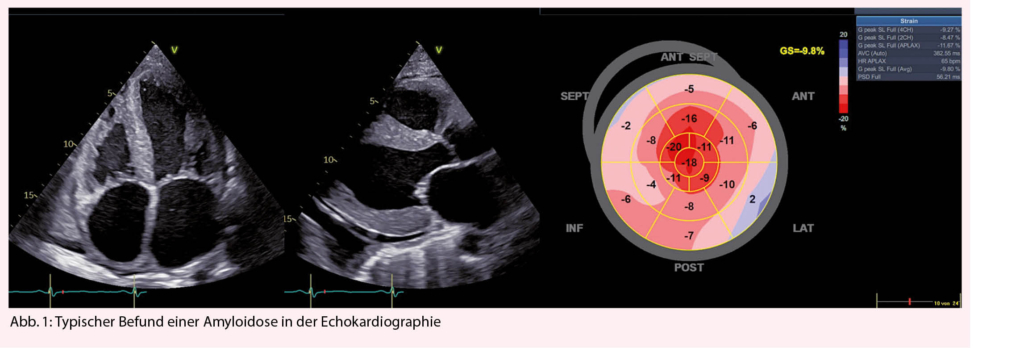

An eine kardiale Amyloidose sollte immer dann gedacht werden, wenn sich ein Patient mit Symptomen einer Herzinsuffizienz präsentiert und einen Echokardiographie- oder MRI-Befund aufweist der typisch für eine Amyloidose ist (Abb. 1 und Tab. 1) (1).

Bei Verdacht auf eine kardiale Amyloidose (Herzinsuffizienz-Beschwerden, typisches Echo oder MRI) sollten zuerst ausführliche Laboruntersuchungen inkl. kardiale Biomarker NT-pro BNP und Troponin (zur Abschätzung der Prognose) und eine Protein-Elektrophorese mit Immunfixation im Serum und Urin sowie Bestimmung der freien Leichtketten im Serum veranlasst werden. Letzteres ist entscheidend für die Unterscheidung zwischen AL und ATTR Amyloidose. Ein EKG sollte geschrieben werden, um die Frage nach Vorhofflimmern und Blockierungen zu beantworten. Die typischerweise beschriebene «low-voltage» findet sich eher bei der AL-Amyloidose, bei der ATTR ist dies jedoch nicht so häufig (ca. 22%), typischer ist dort ein Pseudoinfarktmuster (63%). Bei unauffälliger Immunfixation ist eine AL-Amyloidose praktisch ausgeschlossen (Abb. 2). In diesem Fall sollte eine Technetium Szintigraphie durchgeführt werden. Fällt diese positiv aus, gilt die Diagnose einer ATTR-Amyloidose als gesichert (4), jedoch kann nicht zwischen wtATTR und vATTR unterschieden werden, weswegen eine genetische Testung sinnvoll ist. Diese kann nach Einholen einer Kostengutsprache durch die Krankenkasse durchgeführt werden kann. An eine hereditäre Form sollte insbesondere dann gedacht werden, wenn neurologische Symptome wie Polyneuropathie vorhanden sind. Bei negativer Szintigraphie und persistierend hohem Verdacht auf eine kardiale Amyloidose, sollte eine Endmyokardbiopsie durchgeführt werden (5). Bei pathologischer Immunfixation und Verdacht auf eine kardiale Amyloidose ist die Situation etwas komplizierter, da die Diagnose mittels Biopsie und Nachweis von Amyloid gestellt werden muss. Normalerweise erfolgt bei pathologischer Immunfixation eine hämatologische Abklärung, gelegentlich gelingt der Nachweis von Amyloid schon in der Knochenmarksbiopsie (ca. 50%), ansonsten muss Amyloid an anderen Stellen (typischerweise Bauchfett, Speicheldrüsen, Endomyokard) gesucht und immunhistochemisch bestätigt werden, was gelegentlich herausfordernd sein kann (Abb. 2). Ein wichtiges Problem stellt die hohe Koinzidenz eines MGUS mit der wtATTR Amyloidose im fortgeschrittenen Alter dar.